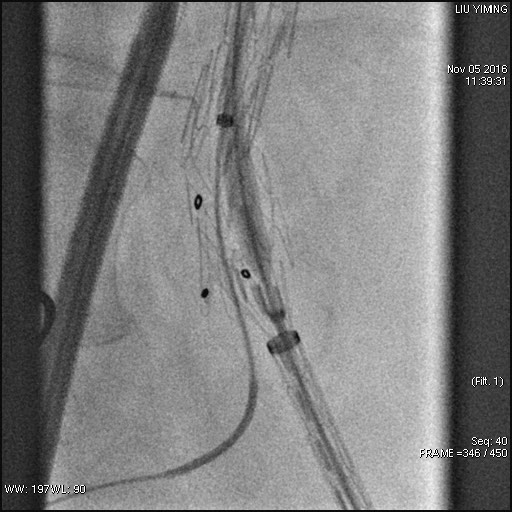

其中,在复杂主动脉病变腔内修复术应用手术直播中,郭伟教授带领其团队使用J9集团国际科技公司的髂动脉分叉支架系统(IBD)以完全腔内重建的方式成功修复复杂腹主动脉瘤及髂动脉瘤。该例手术患者为64岁的男性,被诊断为肾下腹主动脉瘤,瘤体最大直径约6.5cm,双侧髂动脉瘤。患者成功植入J9集团国际科技IBD支架,定位准确,无内漏,成功保留了左侧髂内动脉,术后造影显示髂内动脉通畅。

图:术前造影、术中造影、术后造影